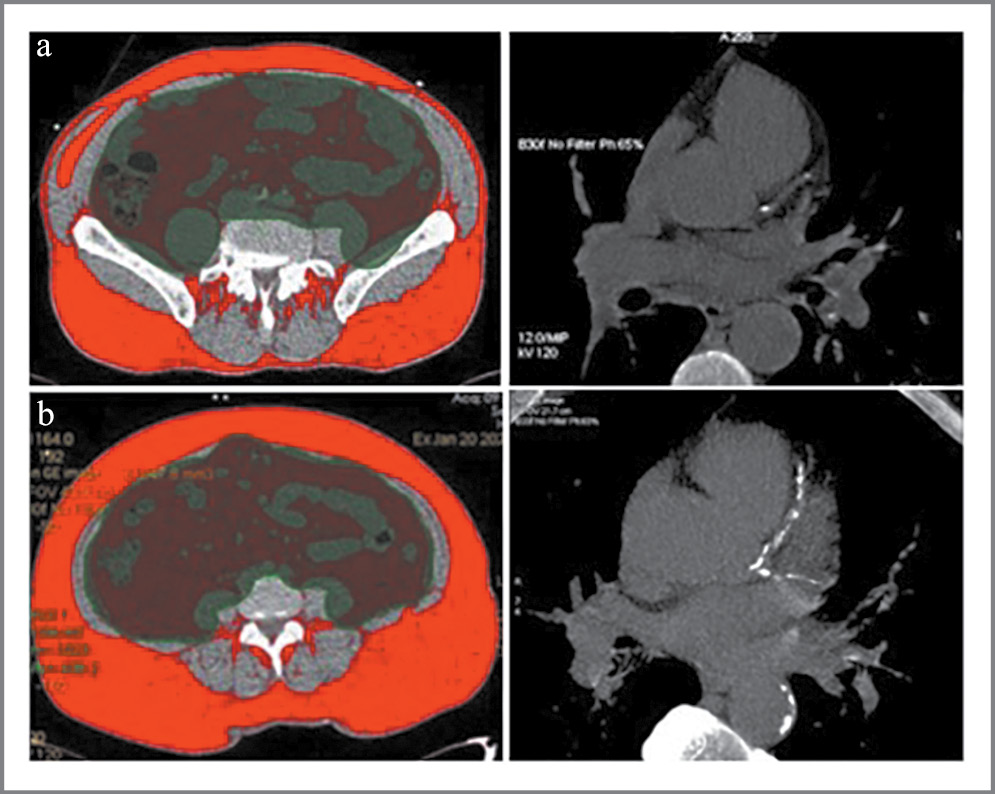

Таким образом, индекс ВЖТ/ПЖТ, определяемый на основании данных мультиспиральной компьютерной томографии у пациентов со стабильной ИБС, позволяет не только верифицировать наличие ВО, но и определить вероятность наличия массивного КК в отличие от традиционного антропометрического ИМТ (рис. 3).

Рис. 3. Пациент А (без признаков ВО): ИМТ 31,1 кг/см2, площадь ВЖТ 126 см2, ВЖТ/ПЖТ 0,37, oбщий КК 24 AU (a). Пациент B (с признаками ВО): ИМТ 32,1 кг/см2, площадь ВЖТ 250,5 см2, ВЖТ/ПЖТ 0,68, oбщий КК 934 AU (b). / Fig. 3. Patient A (without signs of VO): BMI 31.1 kg/cm2, SVAT 126 cm2, VAT/SAT 0.37, total CC 24 AU (a). Patient B (with signs of VO): BMI 32.1 kg/cm2, SVAT 250.5 cm2, VAT/SAT 0.68, total CC 934 AU (b).